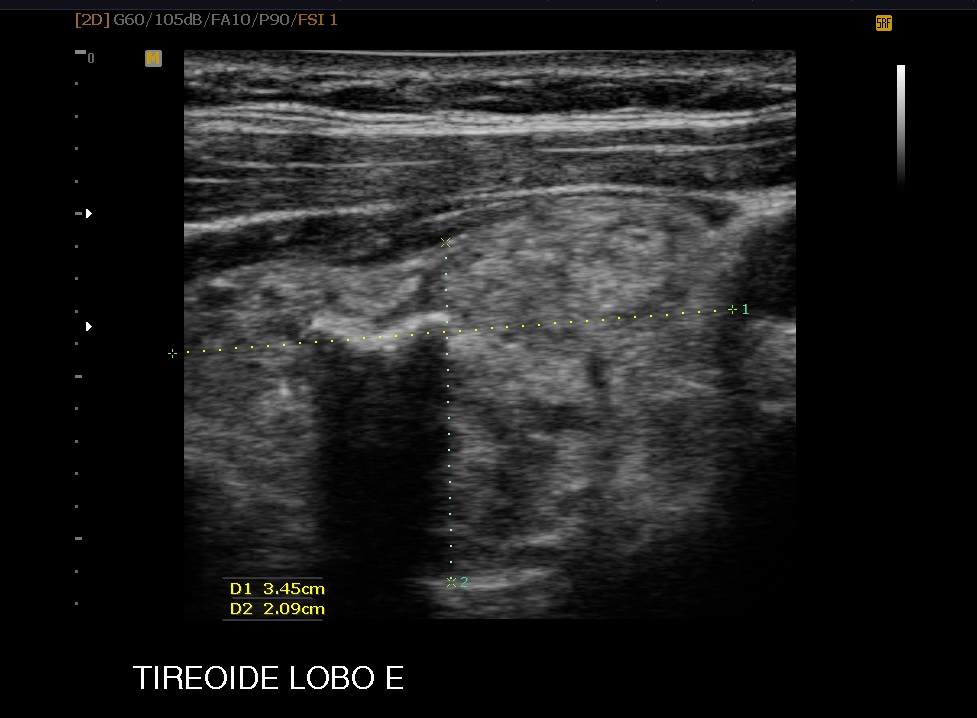

O ultrassom é usado para exames do abdome para avaliação dos rins, fígado, pâncreas, ginecológicos para útero e anexos, para exame dos músculos e articulações, tireóide, mamas,testículos e globo ocular, enfim quase todos os órgãos podem ser estudados pela ultra-sonografia.